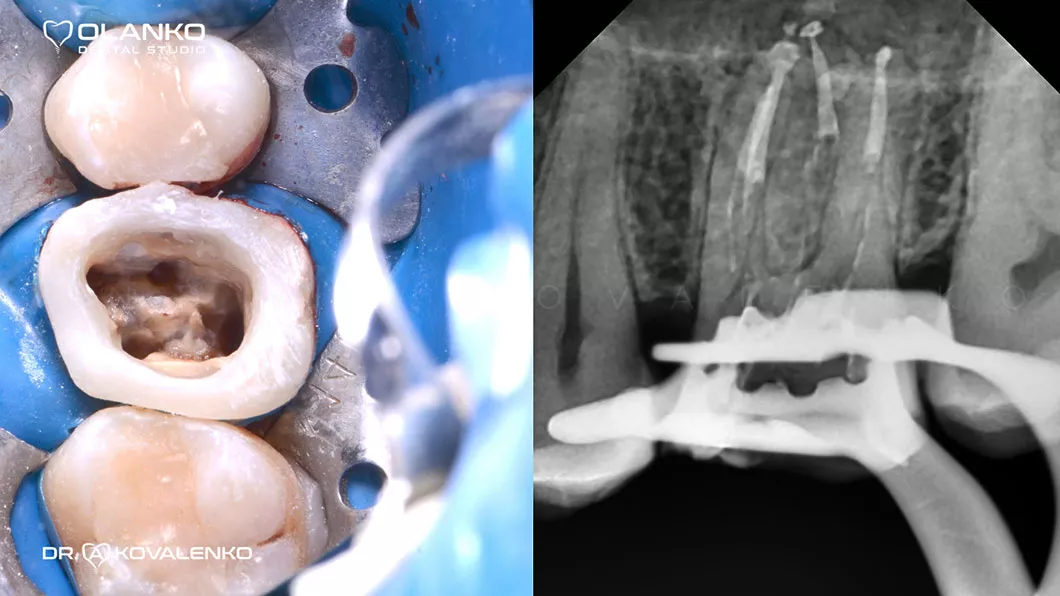

ВІДЕО ЛІКУВАННЯ КОРЕНЕВИХ КАНАЛІВ ЗУБА ПІД МІКРОСКОПОМ ТА ПОДАЛЬШИМ ВІДНОВЛЕННЯ ЗУБА КЕРАМІЧНОЮ КОРОНКОЮ

На сьогоднішній день, лікування зубів з використанням мікроскопу — це золотий стандарт світової стоматологічної практики. Складна система кореневих каналів має дуже малий діаметр та індивідуальну анатомію, тому лікар, який працює без збільшення, майже на дотик, не може якісно їх пролікувати.

Важливою перевагою Olanko dental studio (Оланко) м. Бровари є виконання всіх етапів лікування кореневих каналів тільки під контролем операційного дентального мікроскопу!

Для лікування простих клінічних випадків, як правило, потрібен всього один візит 1,5-2,5 години.

Складні випадки переліковування кореневих каналів, каналів зі складною анатомією, вимагають 2-3 візитів.

Ми маємо величезний клінічний досвід лікування зубів зі складною анатомією (викривленими, склерозованими каналами), а також повторного переліковування каналів з кістою, гранульомами, зламаними інструментами, з подальшими відмінними результатами загоєння хронічних запалень.